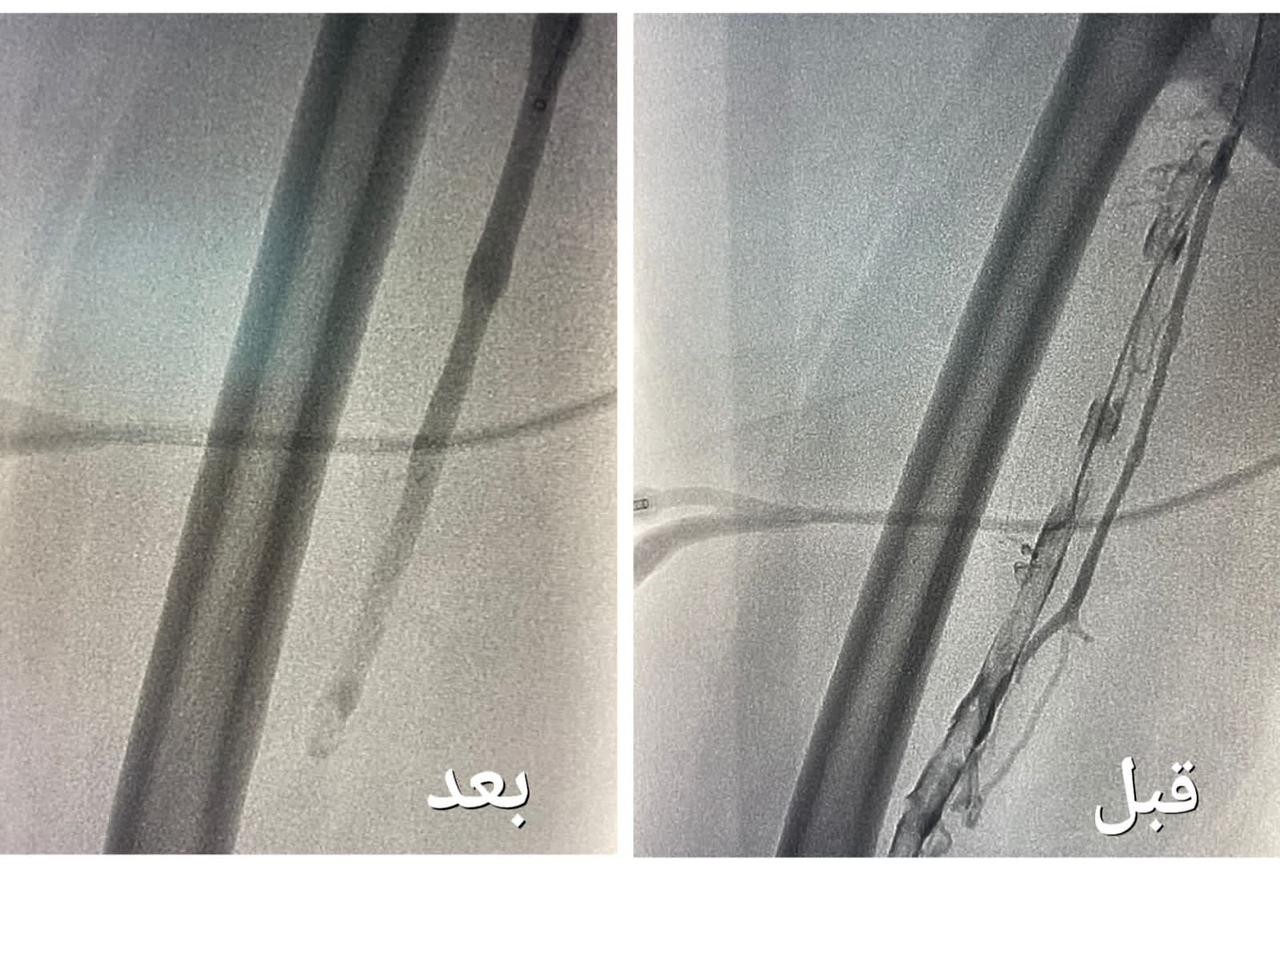

تمكن فريق وحدة الأشعة التداخلية بمجمع الملك عبدالله بجدة من إنهاء معاناة حاجّة هندية تبلغ من العمر ٦٧ عاماً ، و كانت الحاجّة تعاني من جلطة وريدية من مستوى الكاحل إلى مستوى أوردة الحوض الأيمن ، و انتفاخ كامل في القدم مع عدم القدرة على المشي .

وأوضحت "الصحة" أنه بعد إجراء الفحوصات الطبية و الكشف تبين وجود جلطة وريدية من مستوى الكاحل إلى مستوى أوردة الحوض الأيمن ، و انسداد كامل في أوردة القدم اليمنى حتى الحوض ، قرر بعدها الفريق الطبي تنويم المريضة و التنسيق مع فريق وحدة الأشعة التداخلية بشكل عاجل لدراسة الحالة و معالجتها ، و وضع الخطة العلاجية ، لنقلها إلى غرف عمليات الأشعة لإجراء عملية بإستخدام جهاز إزالة الجلطات تحت التخدير الموضعي و التهدئة الواعية .

وقالت الوزارة إن العملية استغرقت نحو ساعتين ، تكللت _ ولله الحمد_ بالنجاح ، تم فيها تركيب فلتر للوريد الأجوف السفلي لمنع انتقال الجلطات للرئة ، و من ثم الدخول للوريد المتجلط في مستوى الكاحل و حقن مواد مذيبة للجلطات ، و قد استخدمت أجهزة نوعية لمثل هذه الحالات والتي تعمل على سحب الجلطات بعد إذابتها و توسعة الأوردة بالبالون لإعادة جريان الدم .